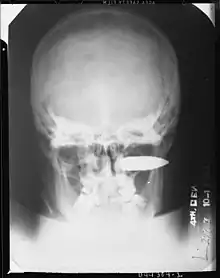

Exemple de traumatisme grave : Blessure de guerre au visage, par balle de mitrailleuse (calibre 0,5), entrée juste au-dessous du sourcil droit. 11 jours après la blessure, le patient a commencé une hémorragie si abondante qu'il a été impossible de mener à bien les procédures d'urgence. Ce patient est alors décédé (seconde guerre mondiale, archives, 4e Hôpital general de l'armée américaine)